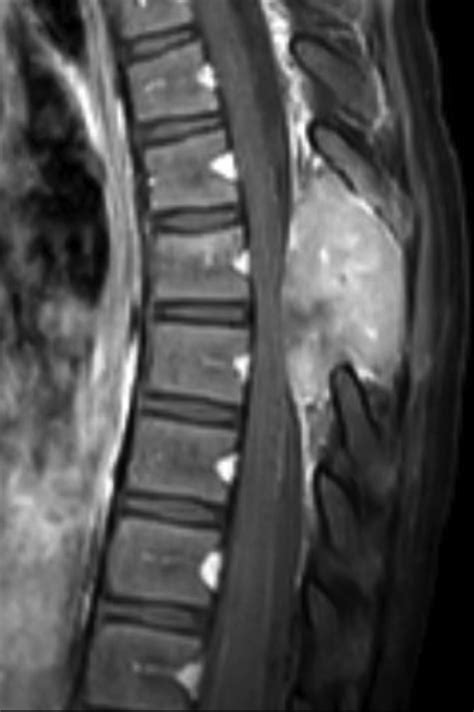

A cancer tumor back diagnosis generally refers to an abnormal growth of cells located within the spinal canal or the bones of the spine (vertebrae). These tumors are classified based on their location: intradural-extramedullary (inside the spinal canal but outside the spinal cord), intramedullary (inside the spinal cord), or extradural (outside the spinal cord, often involving the bone).

Most spinal tumors are actually metastatic, meaning they have traveled to the spine from a primary cancer located elsewhere in the body, such as the lungs, breasts, or prostate. When a tumor grows in the back, it can compress the spinal cord or the nerve roots, leading to a variety of debilitating symptoms that go far beyond simple back pain.

MRI Scan The gold standard for visualizing soft tissues and nerve compression.